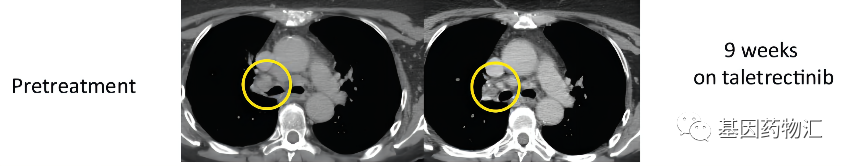

甲状腺乳头状癌:33.4个月,至发布时仍处于缓解

这位TPM3-NTRK1融合突变的转移性甲状腺乳头状癌患者,通过Taletrectinib(AB-106)治疗取得了相当不错的疗效。他用药后的缓解持续时间已经达到了33.4个月,并且至结果发布时,仍在刷新着这个数据,持续保持临床缓解!

他之前已经接受过非常多的治疗,包括甲状腺切除术、放化疗、放射性I-131治疗、索拉非尼治疗,甚至接受过了3个靶向治疗联合或不联合免疫检查点抑制剂的Ⅰ期临床试验。能够继续达到这样长的缓解期,疗效可谓相当出色。